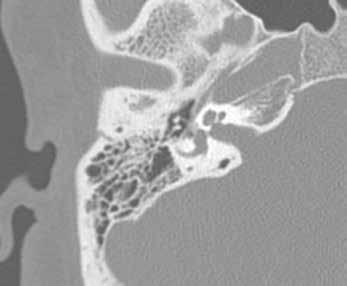

A 34-year-old man presented to the otology clinic complaining of right progressive hearing loss over the previous 4 years. Otoscopic examination revealed a reddish blush visible on the cochlear promontory beyond an intact right tympanic membrane (figure 1). Both 512- and 1024-Hz tuning forks lateralized to the right ear, and bone conduction was greater than air conduction on the right using both tuning forks. Audiometry revealed a moderate conductive hearing loss on the right with absent reflexes.

Computed tomography (CT) was performed, revealing demineralization at the fissula ante fenestram bilaterally (figure 2). At the time of surgery, a fixed stapes was noted, confirming the clinical diagnosis of otosclerosis.

Figure 1. Otoscopy of the right tympanic membrane demonstrates a reddish blush on the cochlear promontory. Figure 2. CT demonstrates demineralization at the fissula ante fenestram on the right, which is present bilaterally.